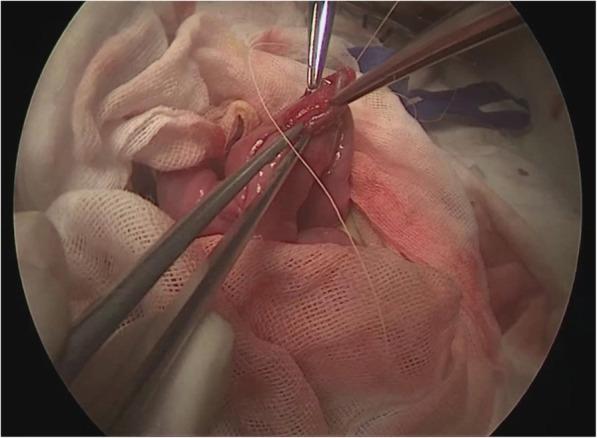

A modified technique of single-incision laparoscopic hepaticojejunostomy for children with choledochal cysts.

To present a modified laparoscopic surgical technique that works to optimize the surgical view in laparoscopic total excision of choledochal cyst in pediatric patients.

METHODS

From June 2015 to June 2017, a total of 48 pediatric cases of choledochal cyst were admitted. Their age ranged from 15 month to 8 years (average 3.5 years). The Todani types were: type I (n = 32) and type IVa (n = 16), according to the diagnostic criteria of ultrasound, abdominal computed tomography (CT) and magnetic resonance cholangiopancreatography (MRCP).

RESULTS

Total cystic excision with hepaticoenterostomy was accomplished laparoscopically in 48 cases with our transumbilical single -incision method without conversion to open surgery. Average duration of operation was 200 min (range 170-240 min), average intraoperative blood loss was 9 ml (range 6-14 ml) without the need for blood transfusion. The 72-h postoperative ultrasound reported no abdominal effusion, when the intraperitoneal drainage tube was removed. There was no postoperative complication during the 6 months of follow-up.

CONCLUSIONS

We accomplished the same postoperative outcome in laparoscopic total cyst excision with our modified method as that with conventional laparoscopic surgery. This technique allows the operator to have a stabilized surgical view without needing to rely on an assistant to hold up the liver lobe for larger operative space.